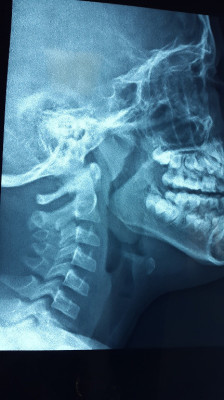

Hipertrofia Obstructiva de Adenoides y Amígdalas